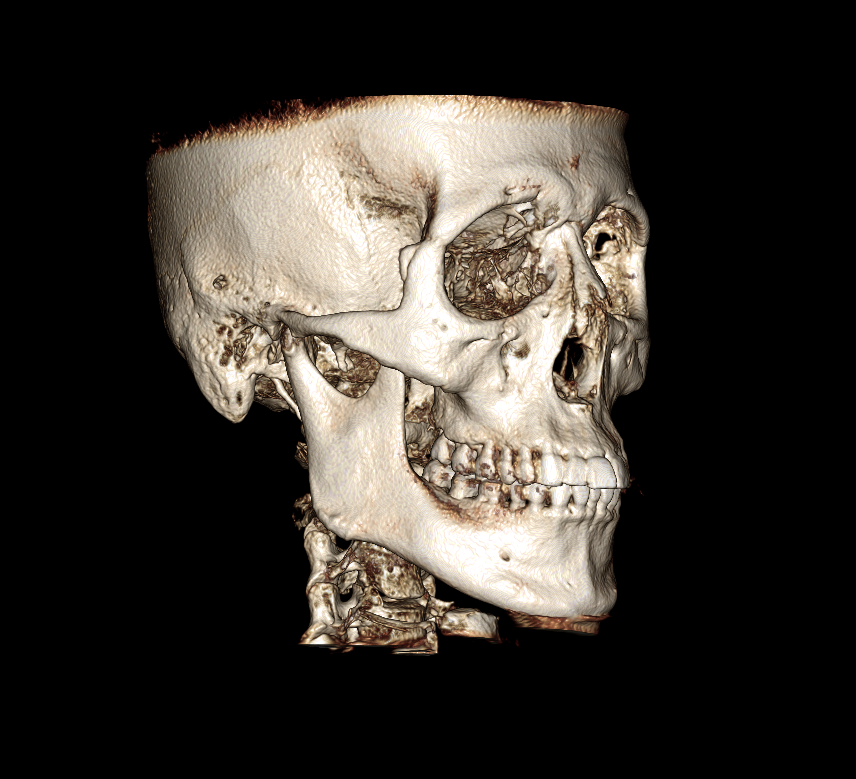

| 主訴 | 前歯のがたつきと出っ歯が気になる |

初診時の画像

確かにお顔を拝見すると、上の歯も下の歯もやや出ている感じがしますね。このような場合の治療法としては基本的には真ん中の歯の抜歯を行い、そのスペースを使用して、前歯をひっこめるのが定石です。もしくは少しずつ奥歯を後ろに移動し、さらに少し歯を削ることでスペースを作り前歯を後ろに引くのも一つです。大きく前歯をひっこめる場合にはやはり抜歯が妥当です。もう一つのご質問のマウスピース矯正で治療が可能かという質問ですが、それは可能です。しかし抜歯を行う場合には、マウスピース矯正だけでなくワイヤー矯正も併用する可能性があります。